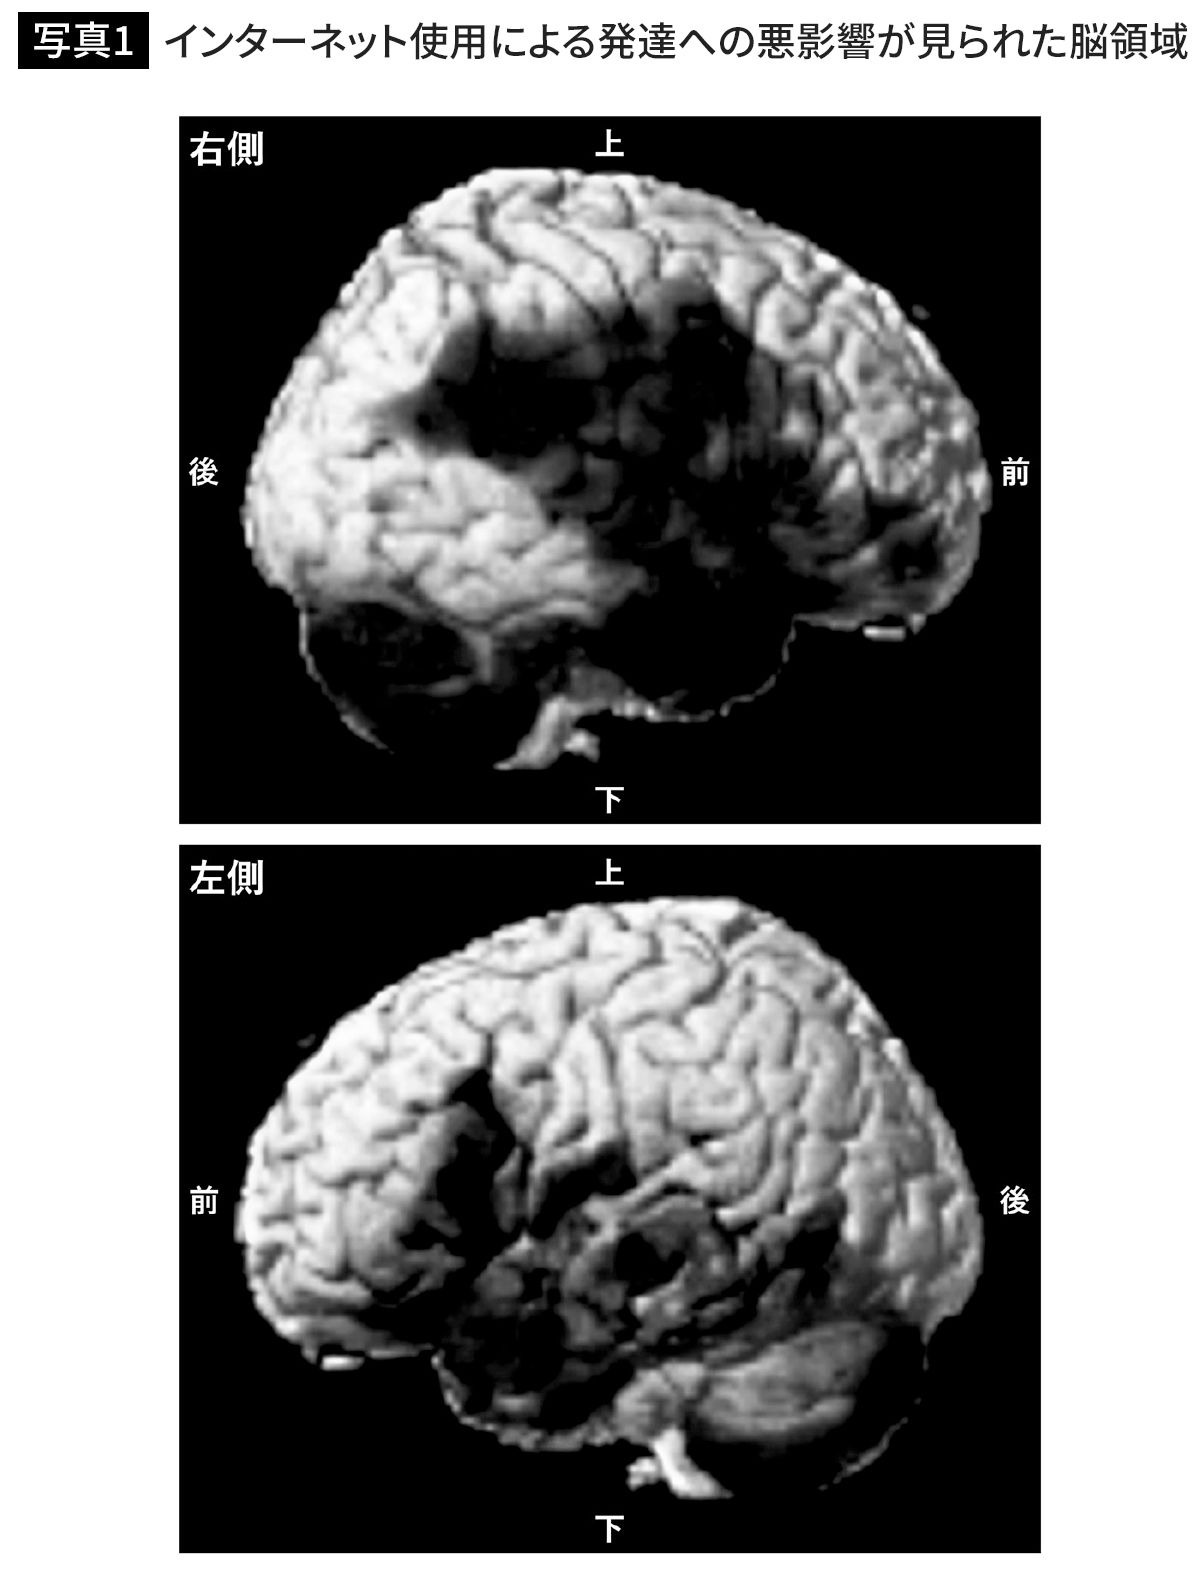

中学入学時にスマホを買い与えると脳の発達が小6で止まる…スマホを毎日使う子を3年間追った衝撃の結果

出典=『

スマホはどこまで脳を壊すか

』